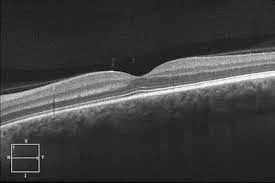

An OCT (optical coherence topography) scan pictured above and below, allows eye care providers to visualize the layers of the retina individually. These are commonly performed on individuals with macular degeneration or diabetic eye disease.